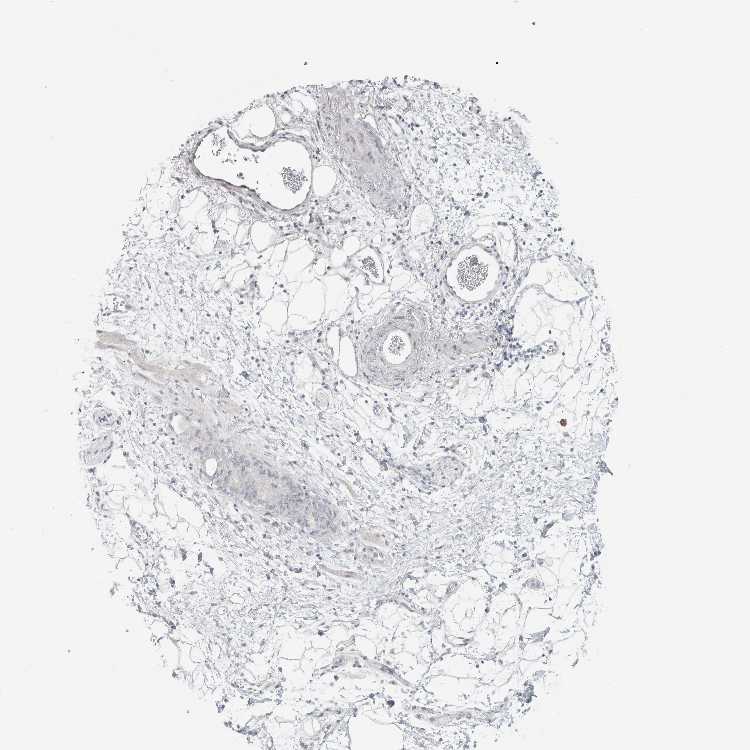

SOFT TISSUE 2 - Antibody stainingi

Antibody staining in the annotated cell types in the current human tissue is reported as not detected, low, medium, or high, based on conventional immunohistochemistry profiling in selected tissues. This score is based on the combination of the staining intensity and fraction of stained cells.

Each image is clickable and will lead to virtual microscopy that enables deeper exploration of all samples and also displays staining intensity scores, fraction scores and subcellular localization as well as patient and tissue information for each sample.

Antibody HPA011284Antibody CAB026403

Fibroblasts Not detectedNot detected

Peripheral nerve Not detectedNot detected